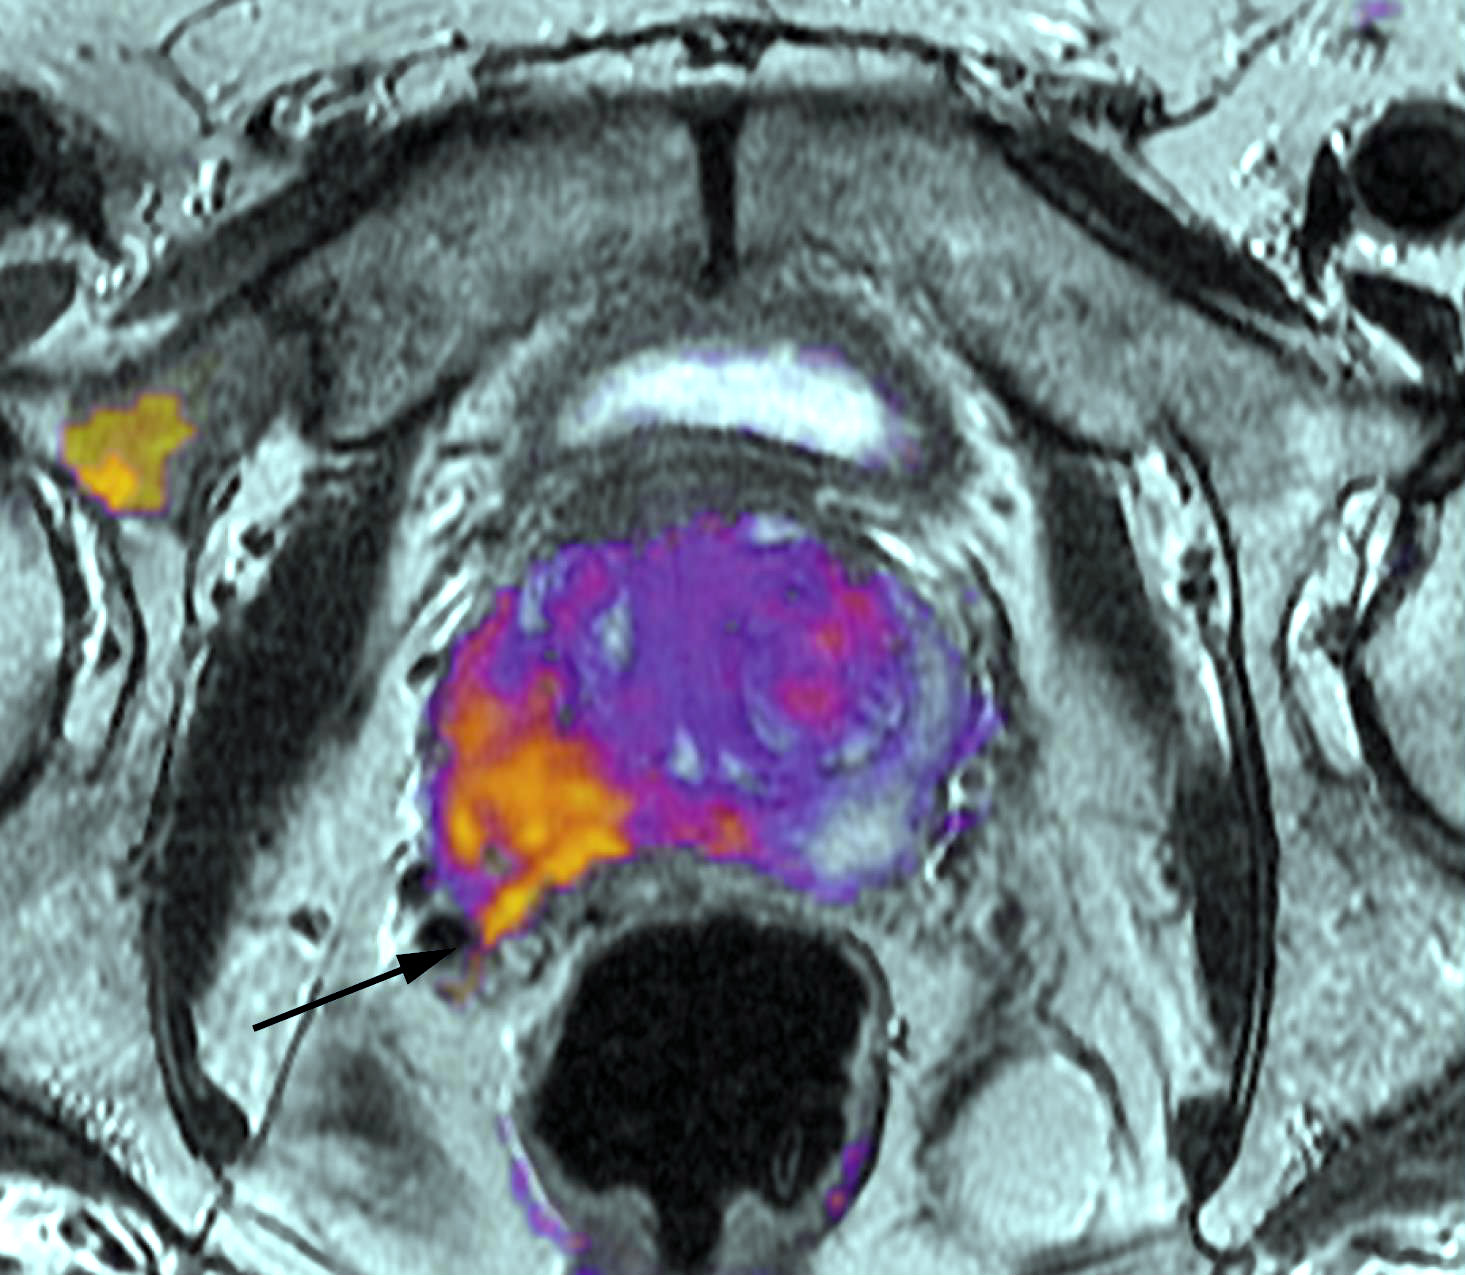

¿La vasectomía produce cáncer de próstata?

Una extensa revisión de la evidencia muestra una débil asociación en los estudios mejor diseñados, con escaso impacto sobre el riesgo absoluto de la enfermedad. JAMA Internal Medicine, 17 de julio de 2017